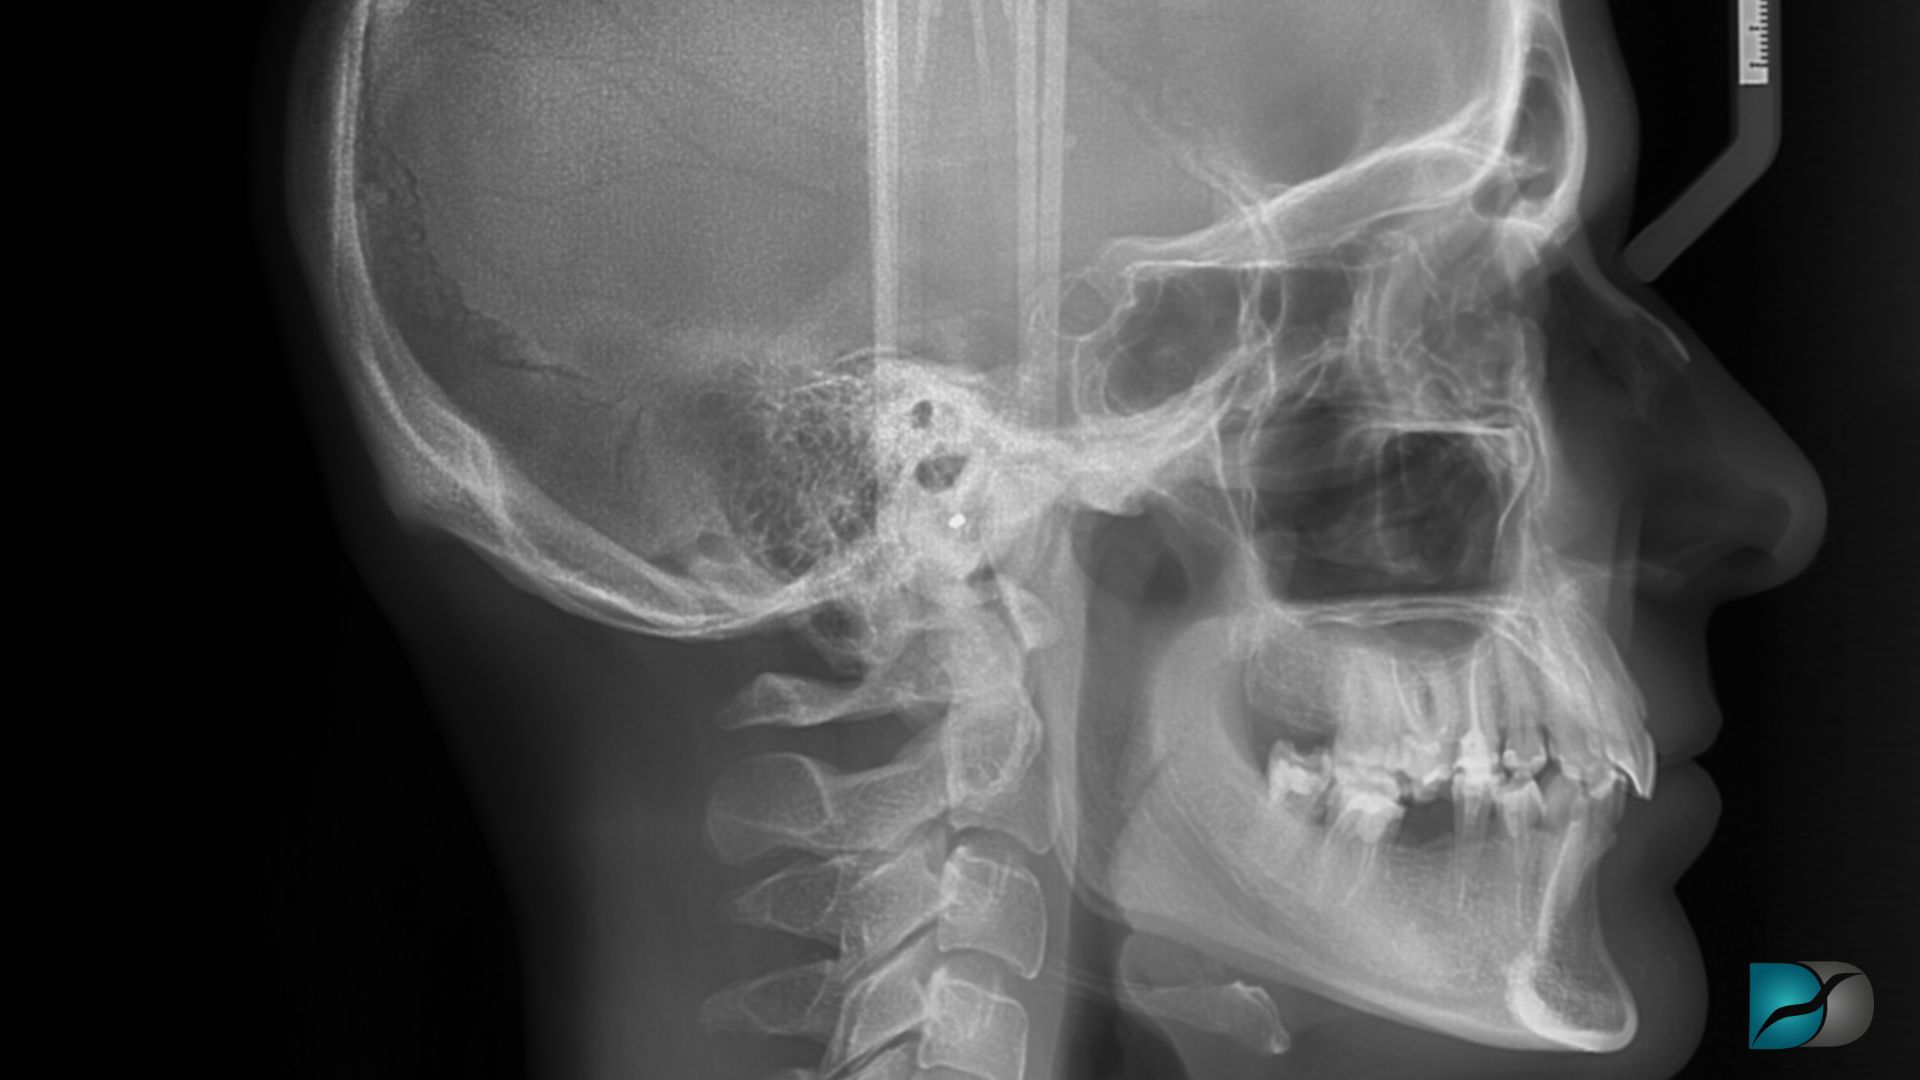

Popularisée par la chaîne YouTube Orthotropics, cette technique est simple à réaliser. En plaçant sa langue contre le palais sans toucher les dents de devant et en gardant la bouche fermée, elle est réputée modeler le bas du visage en réalignant l’axe menton – mâchoires pommettes, sans passer par la case chirurgie.